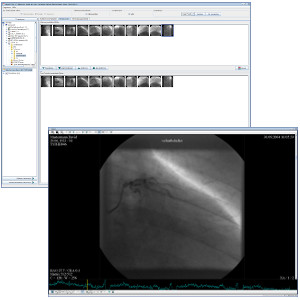

TM-PACS

Le PACS permet la compression, la sécurisation, le stockage et la visualisation d'images radiologiques avec des outils d’affichage et de visualisation pointus (zoom, loupe, annotations, mesure de distance, suivi de mesures, etc.). L’utilisateur peut visualiser à la fois des images coronarographiques, des images PET de médecine nucléaire, ainsi que de l’imagerie plus classique (IRM, CT scan, échographie, etc.). L’utilisation de labels associés aux examens permet de constituer des groupes d’examens et d’y accéder au moyen d’un simple clic. Un système de recherche personnalisée permet de retrouver le dossier du patient ou l'examen désiré de manière très rapide. L’affichage est quant à lui optimisé afin de permettre un affichage multi-écrans sans oublier l’intégration des logiciels RIS et PACS, installés sur les mêmes stations de diagnostic.